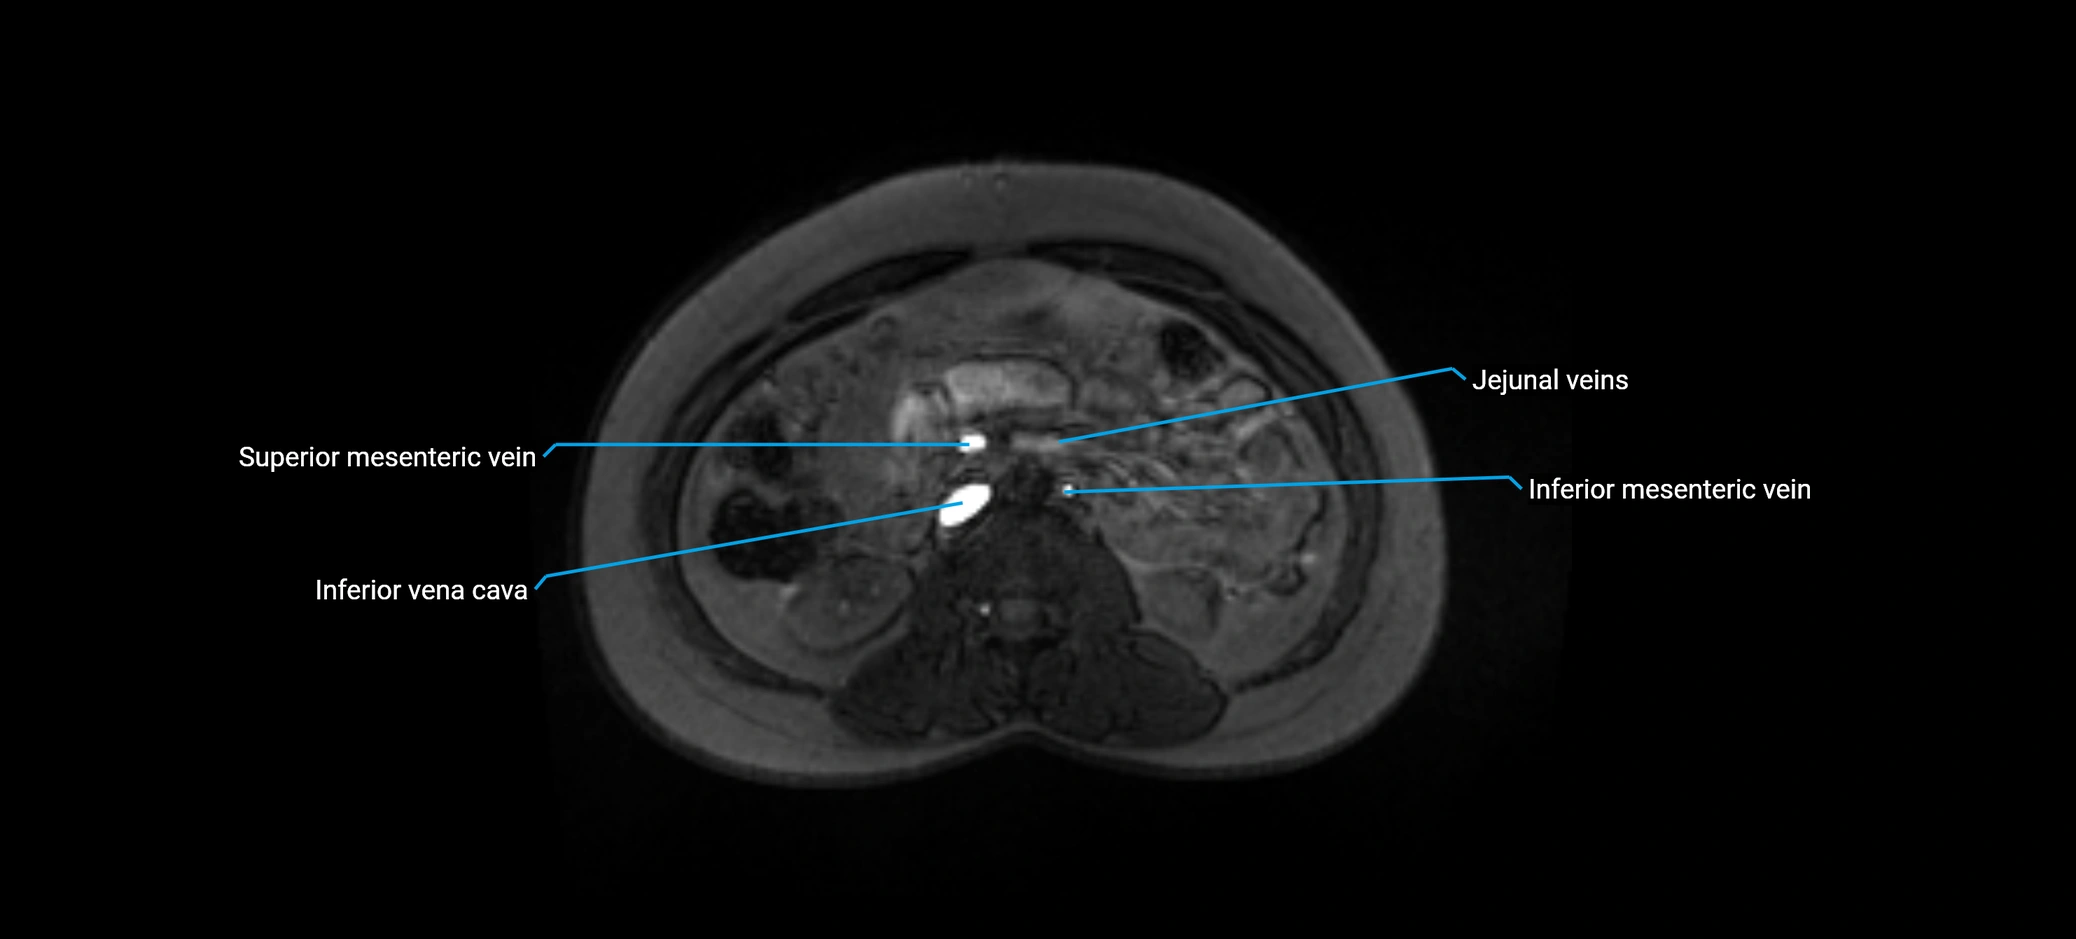

MRI image

image